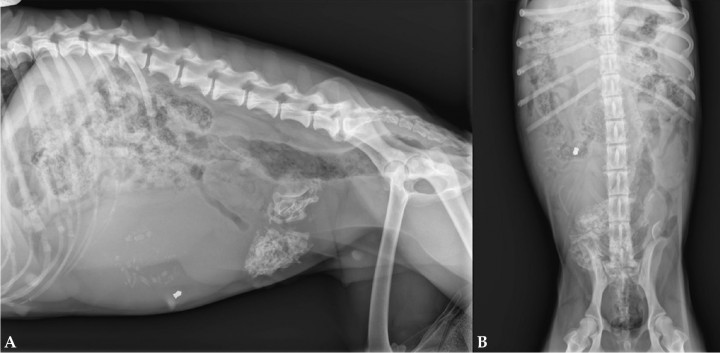

Se presenta en consulta una perra Setter Inglés de 18 kg, adulta, de edad desconocida, procedente de una protectora de animales, con sintomatología inespecífica, ligera apatía y sospecha de gestación. Los hallazgos clínicos más relevantes fueron mucosas ligeramente congestivas, frecuencia cardiaca dentro de la normalidad (88 lpm), pulso femoral fuerte, temperatura de 38,2 ºC, abdomen distendido sin signos de dolor y sin descarga vaginal apreciable. El hemograma reveló una leve anemia (hematocrito 35 %; valor de referencia: 37,3-61,7 %) y no se observaron alteraciones en la bioquímica sérica. Se realizaron radiografías de la cavidad abdominal (Fig. 1).

<p>Radiografías del abdomen. (<strong>A</strong>) Proyección laterolateral derecha. (<strong>B</strong>) Proyección ventrodorsal.</p>

Radiografías del abdomen. (A) Proyección laterolateral derecha. (B) Proyección ventrodorsal.

En ambas proyecciones se visualiza buena definición de serosas y se aprecian varias masas de morfología tubular y opacidad tejido blando que ocupan gran parte del abdomen medio y caudal, produciendo un efecto masa con desplazamiento dorsocraneal de estómago, asas intestinales y colon. A nivel del abdomen medio ventral y caudal se observan unas estructuras de opacidad hueso, así como otra de opacidad metal cuya morfología es compatible con la de un balín localizado en abdomen medio ventral, en el lado derecho (Fig. 2).

<p>Mismas radiografías de la Figura 1. Se observan masas de morfología tubular y opacidad tejido blando que generan efecto masa (flechas amarillas), así como estructuras de opacidad hueso (flechas rosas) en su interior.</p>

Mismas radiografías de la Figura 1. Se observan masas de morfología tubular y opacidad tejido blando que generan efecto masa (flechas amarillas), así como estructuras de opacidad hueso (flechas rosas) en su interior.